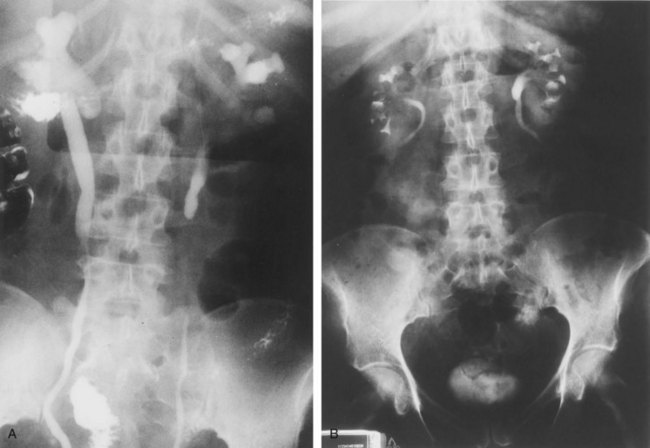

In most RPF patients, the clinical symptoms are generally nonspecific, and physical examination is usually unrevealing. Laboratory evaluation may reveal an elevated erythrocyte sedimentation rate, moderate leukocytosis, anemia, and variable renal insufficiency with associated electrolyte abnormalities. If the overall renal function is normal, an excretory urogram (EVU) or more commonly computed tomography (CT) with contrast may be performed. Typical EVU findings include hydronephrosis with medial deviation of the proximal ureter and midureter and a smoothly tapered ureter at the level of obstruction. Urinary obstruction is usually bilateral, but unilateral cases have been described. Uncommonly, there are patients with symptoms of urinary obstruction but little hydronephrosis on imaging. CT scan typically reveals hydronephrosis associated with a well-delineated retroperitoneal soft tissue mass enveloping the great vessels and the ureters (Fig. 41–36). If the patient has significant renal impairment, a retrograde pyelogram may be performed. In the radiographic evaluation of RPF, magnetic resonance imaging (MRI) can also be helpful because the mass itself has characteristic T1- and T2-weighted images. Retroperitoneal fibrosis is characterized as a diffusely low signal intensity on T1-weighted imaging, although the T2 signal may vary considerably, with high signal intensity consistent with active disease (Fig. 41–37A and B). With treatment, T2 signal often diminishes and thus provides a measure of therapeutic efficacy. Moreover, gadolinium enhancement may also prove valuable in assessing the response to treatment because associated decreases in gadolinium contrast enhancement should also be expected following appropriate therapy (Cronin et al, 2008). If a kidney is suspected to be nonfunctioning, differential renography should be considered to determine renal function because it may affect surgical planning. Representative biopsies of the mass should be obtained percutaneously or at the time of open or laparoscopic ureterolysis to rule out malignancy and allow one to proceed with treatment for RPF.

Figure 41–38 A, Preoperative intravenous pyelogram (IVP) of a patient with idiopathic retroperitoneal fibrosis, showing bilateral hydronephrosis with medial deviation of the ureters. B, Postoperative IVP of the same patient following surgical ureterolysis with intraperitoneal omental wrapping.